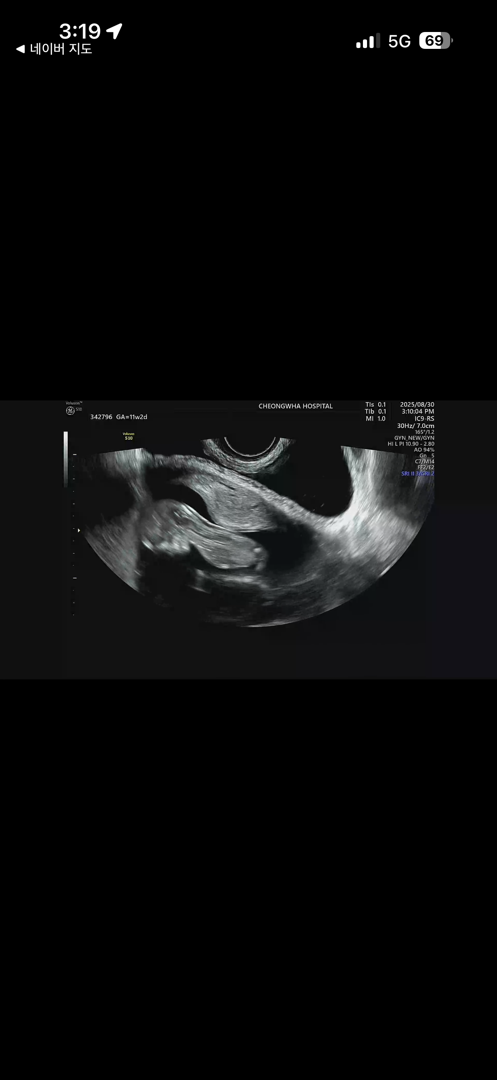

11주2일 초음파인데요..애기가 이렇게 있을수도 있나요..?

너무 냅다 엎드려 있는데 이시기 애기들보면 각도법이니 해서 보던데... 저렇게 엎드려 있음..ㅋㅋ ㅜㅜㅜ 왜 저러고 있었을까요... 젤리곰땐 서있더니..ㅋㅋ

이러저리 움직이고 왔다갔다하더라구요 ㅎㅎㅎ